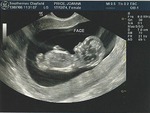

Когда тебе показывают этот комочек, который всего чуть больше 4см, но уже такой родной и любимый. Показали нашего малыша мне и покатились слезы

слезы радости! Виден каждый пальчик даже

Врач сказала, что малыш очень активный. На экране он очень шустро шевелился как мне показалось. Все развивается по сроку, никаких отклонений нет и это самое главное!!!

мы на узи были 47мм. теперь будем быстро рости